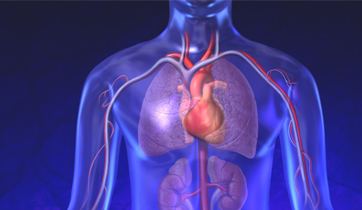

Diastolic Cardiac Insufficiency

Sanofi

ScienceProd, Paris

The Angiotensin - Aldosterone - Renin system is triggered by the thickening of the left ventricle and improper filling of the venticular chamber. This triggers the release of aldosterone, noradrenaline, and angiotensin II which binds to fibroblasts, releasing collagen and increasing myofibril rigidity.

Natracor; hBNP MOA

Scios Pharmaceuticals

Adair Greene Advertising

Natracor treats congestive heart failure triggered by the renin - angiotensin - aldosterone system which causes sodium and fluid retention and vaso-constriction. hBNP is a regulatory hormone, which binds to Guanylate cyclase receptors to reverse effects.